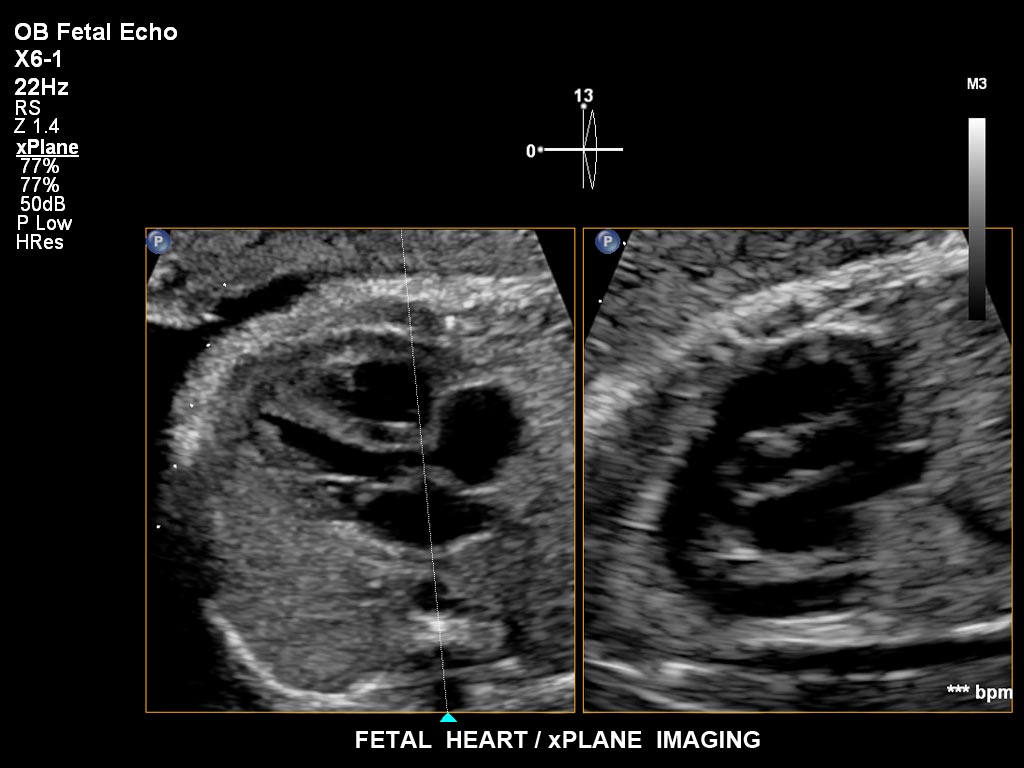

• X6-1 PureWave-xMATRIX Schallkopf für diagnostische Anforderungen, die über die 2D-Bildgebung hinausgehen, setzt mit PureWave neue Maßstäbe u.a. bei der Live-Volumenbildgebung und Live-Bildgebung in zwei Ebenen gleichzeitig